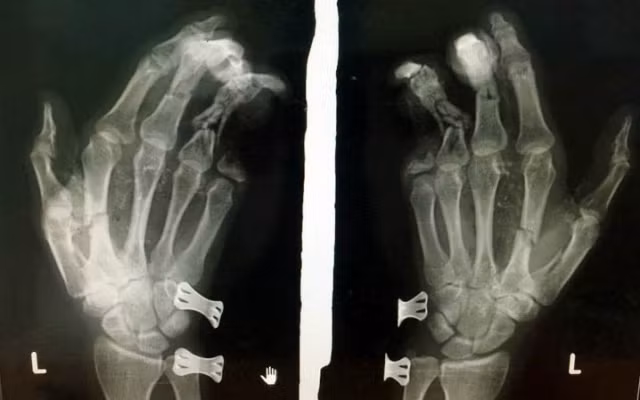

Phim chụp bàn tay của bệnh nhân bị tổn thương do điện thoại phát nổ.

Ngày 27-5, Bệnh viện đa khoa II Lâm Đồng (đóng tại TP Bảo Lộc) tiếp nhận bệnh nhân L.T.D (37 tuổi, ngụ tỉnh Đồng Nai; tạm trú TP Bảo Lộc) nhập viện trong tình trạng bàn tay trái bị thương nặng, vết thương hở. Bệnh nhân được kịp thời sơ cứu, chụp phim và tiến hành phẫu thuật khâu lại vết thương.

Thông tin ban đầu, trưa cùng ngày, anh D sử dụng điện thoại di động vừa cắm sạc pin, vừa chơi game tại nhà trọ thì điện thoại bất ngờ phát nổ khiến bàn tay trái anh D dập nát, tổn thương nặng, ngón út bị mất hai đốt. Ngay sau khi vụ việc xảy ra, người dân đã đưa nạn nhân đến bệnh viện cấp cứu.